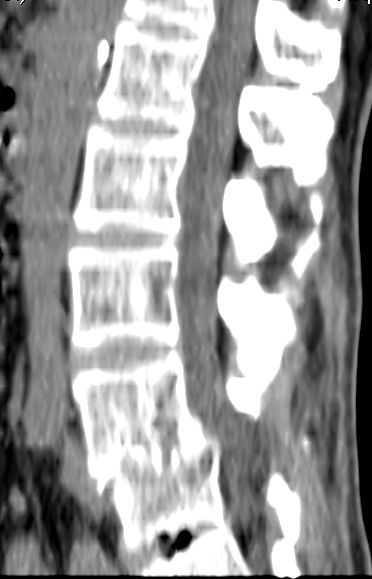

以下是引用余辉在2007-9-4 21:00:00的发言:[br]椎体棘突有点异常(像是被切割了),不知有否手术史,如椎体融合术等。单纯的退行性变可以出现椎间隙变窄,但同时一般会出现椎体上下缘的硬化增生,且椎体间完全融合的机率更小,本例椎体完全融合且椎体上下皮质缘破坏掉了,如果没有手术史,就应该考虑椎间盘炎性病变了,且椎体棘突及棘间韧带的变化也并不是不支持这个,多数小关节也融合了,且其形态也容易让人联想到如强脊炎及类风关等病变。[br][br][本贴已被 余辉 于 2007-9-4 21:03:55 修改过]

以下是引用chry3在2007-9-4 20:42:00的发言:[br]椎间盘病史?是什么样的病史,无双下肢放射痛,那就不是椎间盘突出了。是感染、什么性质的?[br]从图象看椎间隙消失,椎间盘组织未见,锥体滑脱是因为椎间盘溶解造成的[br]l4、5椎体骨质结构未见异常,l5上缘是l4的长期压迫所致[br]还是考虑椎间盘感染,结核。[br]